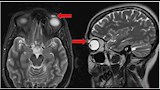

2- عدوى أميبية "آكلة للدماغ" بسبب وعاء نيتي

أصيبت سيدة أمريكية تبلغ من العمر 69 عامًا بعدوى نادرة قاتلة بسبب أميبا تُدعى بالاموثيا ماندريلاريس، نتيجة استخدامها ماء الصنبور في تنظيف الجيوب الأنفية عبر وعاء نيتي، وبدأت الأعراض بطفح جلدي وانتهت بنوبة عصبية حادة، وتبين لاحقًا أن العدوى أصابت دماغها.